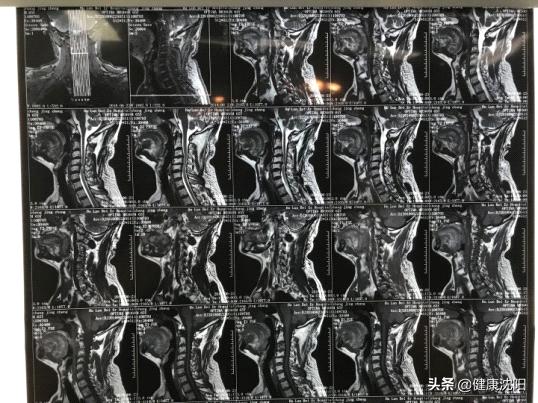

除了颈椎X线平片之外,还有许多特殊的影像学检查方法:

如CT、核磁共振(MRI)等,以及其他作为功能检测的肌电图、诱发电位、脑血流图等。